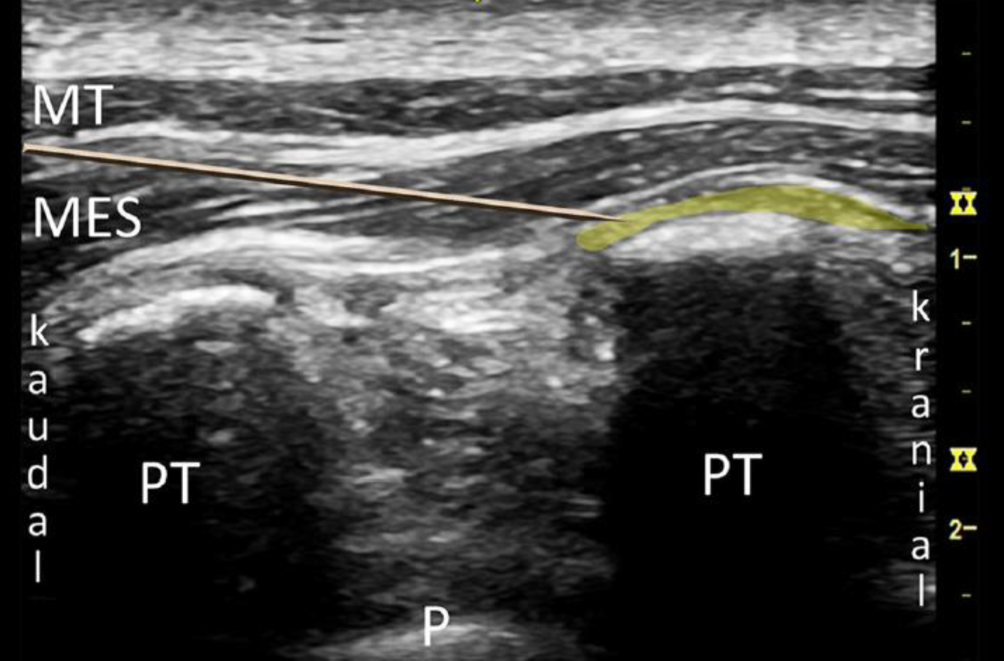

Bei der PVB wird ein Lokalanästhetikumdepot in den Paravertebralraum eingebracht. Hierzu werden Patient*innen in Seitenlage, Bauchlage oder eine sitzende Position gebracht. Sonographisch wird lateral des Processus spinosus zwischen Rippe und Querfortsatz die interne Interkostalmembran dargestellt. Dies kann in transversaler und sagittaler Schallausrichtung erfolgen, mit anschließender Punktion „in plane“ zum Schallkopf, entweder von lateral oder kranial kommend (Abb. 1). Bei korrekter Lage der Spitze der Punktionskanüle im Paravertebralraum tritt häufig ein Widerstandsverlust auf, und bei der Injektion weitet sich der Paravertebralraum mit konsekutiver Verschiebung der Pleura nach ventral (Abb. 2). Für einen Single shot oder das initiale Aufspritzen des Katheters können 15–20 ml 0,2- bis 0,5 %ige Ropivacainlösung verwendet werden; beim katheterbasierten Verfahren sollte die Laufrate maximal 5–6 ml/h betragen [31].

Abb. 1

Anlage einer Paravertebralblockade in sagittaler (a) und transversaler (b) Schallausrichtung. (Aus Steinfeldt et al. [31])

Abb. 2

Sonographische Darstellung einer sagittalen thorakalen Paravertebralblockade. PT Processus transversus, P Pleura, LCT Lig. costotransversarium superius. Lokalanästhetikum gelb dargestellt. (Aus Steinfeldt et al. [31])